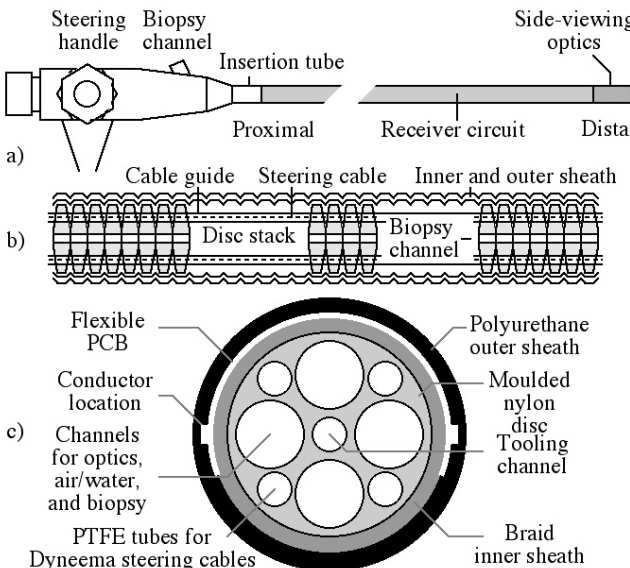

Richard Syms, Evi Kardoulaki and Ian Young

Simon Taylor-Robinson, Chris Wadsworth and Marc Rea (St Mary’s Hospital)

We have developed a magnetic resonance imaging duodenoscope, by combining non-magnetic endoscope components with a thin-film receiver based on a magneto-inductive waveguide. The waveguide elements consist of figure-of-eight shaped inductors formed on either side of a flexible substrate and parallel plate capacitors that use the substrate as a dielectric. Operation has been simulated using equivalent circuit models and by computation of sensitivity patterns. Circuits have been fabricated for operation at 127.7 MHz by double-sided patterning of copper-clad Kapton and assembled onto non-magnetic flexible endoscope insertion tubes. Operation has been verified by bench testing and by 1H MRI at 3T using phantoms. The receiver can form a segmented coaxial image along the length of the endoscope, even when bent, and shows a signal-to-noise-ratio advantage over a surface array coil up to three times the tube diameter at the tip. Initial immersion imaging experiments have been carried out and confirm an encouraging lack of sensitivity to RF heating.

|---|

| Mechanical arrangement of metameterial endoscope. |

|

|---|

| Electrical layout of thin film PCB (a), and equivalent circuit models for imaging (b) and electrical testing (c). |